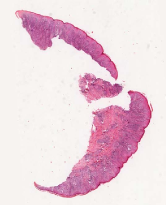

We demonstrate our WSI creation workflow on Leishmaniasis cases, as shown in Figures 1 and 4. An expert pathologist reviewed the cases and annotated granulomas as well as LD bodies on the stitched images and our generated images in Figure 4. To show generalizability of our approach, we also show results on core biopsies of breast, duodenum, stomach, liver, and lymph nodes (Figure 5).

Curated dataset. Skin biopsies from 12 patients diagnosed with cutaneous leishmaniasis (spanning the disease differentiation spectrum) were acquired from Agha Khan University with Internal Review Board approval # 2024-9038-28175. Six of these biopsies, stained with hematoxylin & eosin (H&E), were scanned using Huron’s TissueScope digital scanner at 40X. A cheap-yet-clinical grade ($200) microscope (BS-2020MD Digital Microscope from BestScope International Limited, China) with a built-in digital 1.3 megapixel CMOS USB camera and 1W 5-LED illumination with Halogen Lamp 6V/20W was then used to capture videos for all 12 skin biopsies at 10X resolution. To show generalizability of our whole-slide image creation workflow for other common pathologies beyond cutaneous leishmaniasis, we also acquired videos for core biopsies of breast, liver, duodenum, stomach, and lymph node.